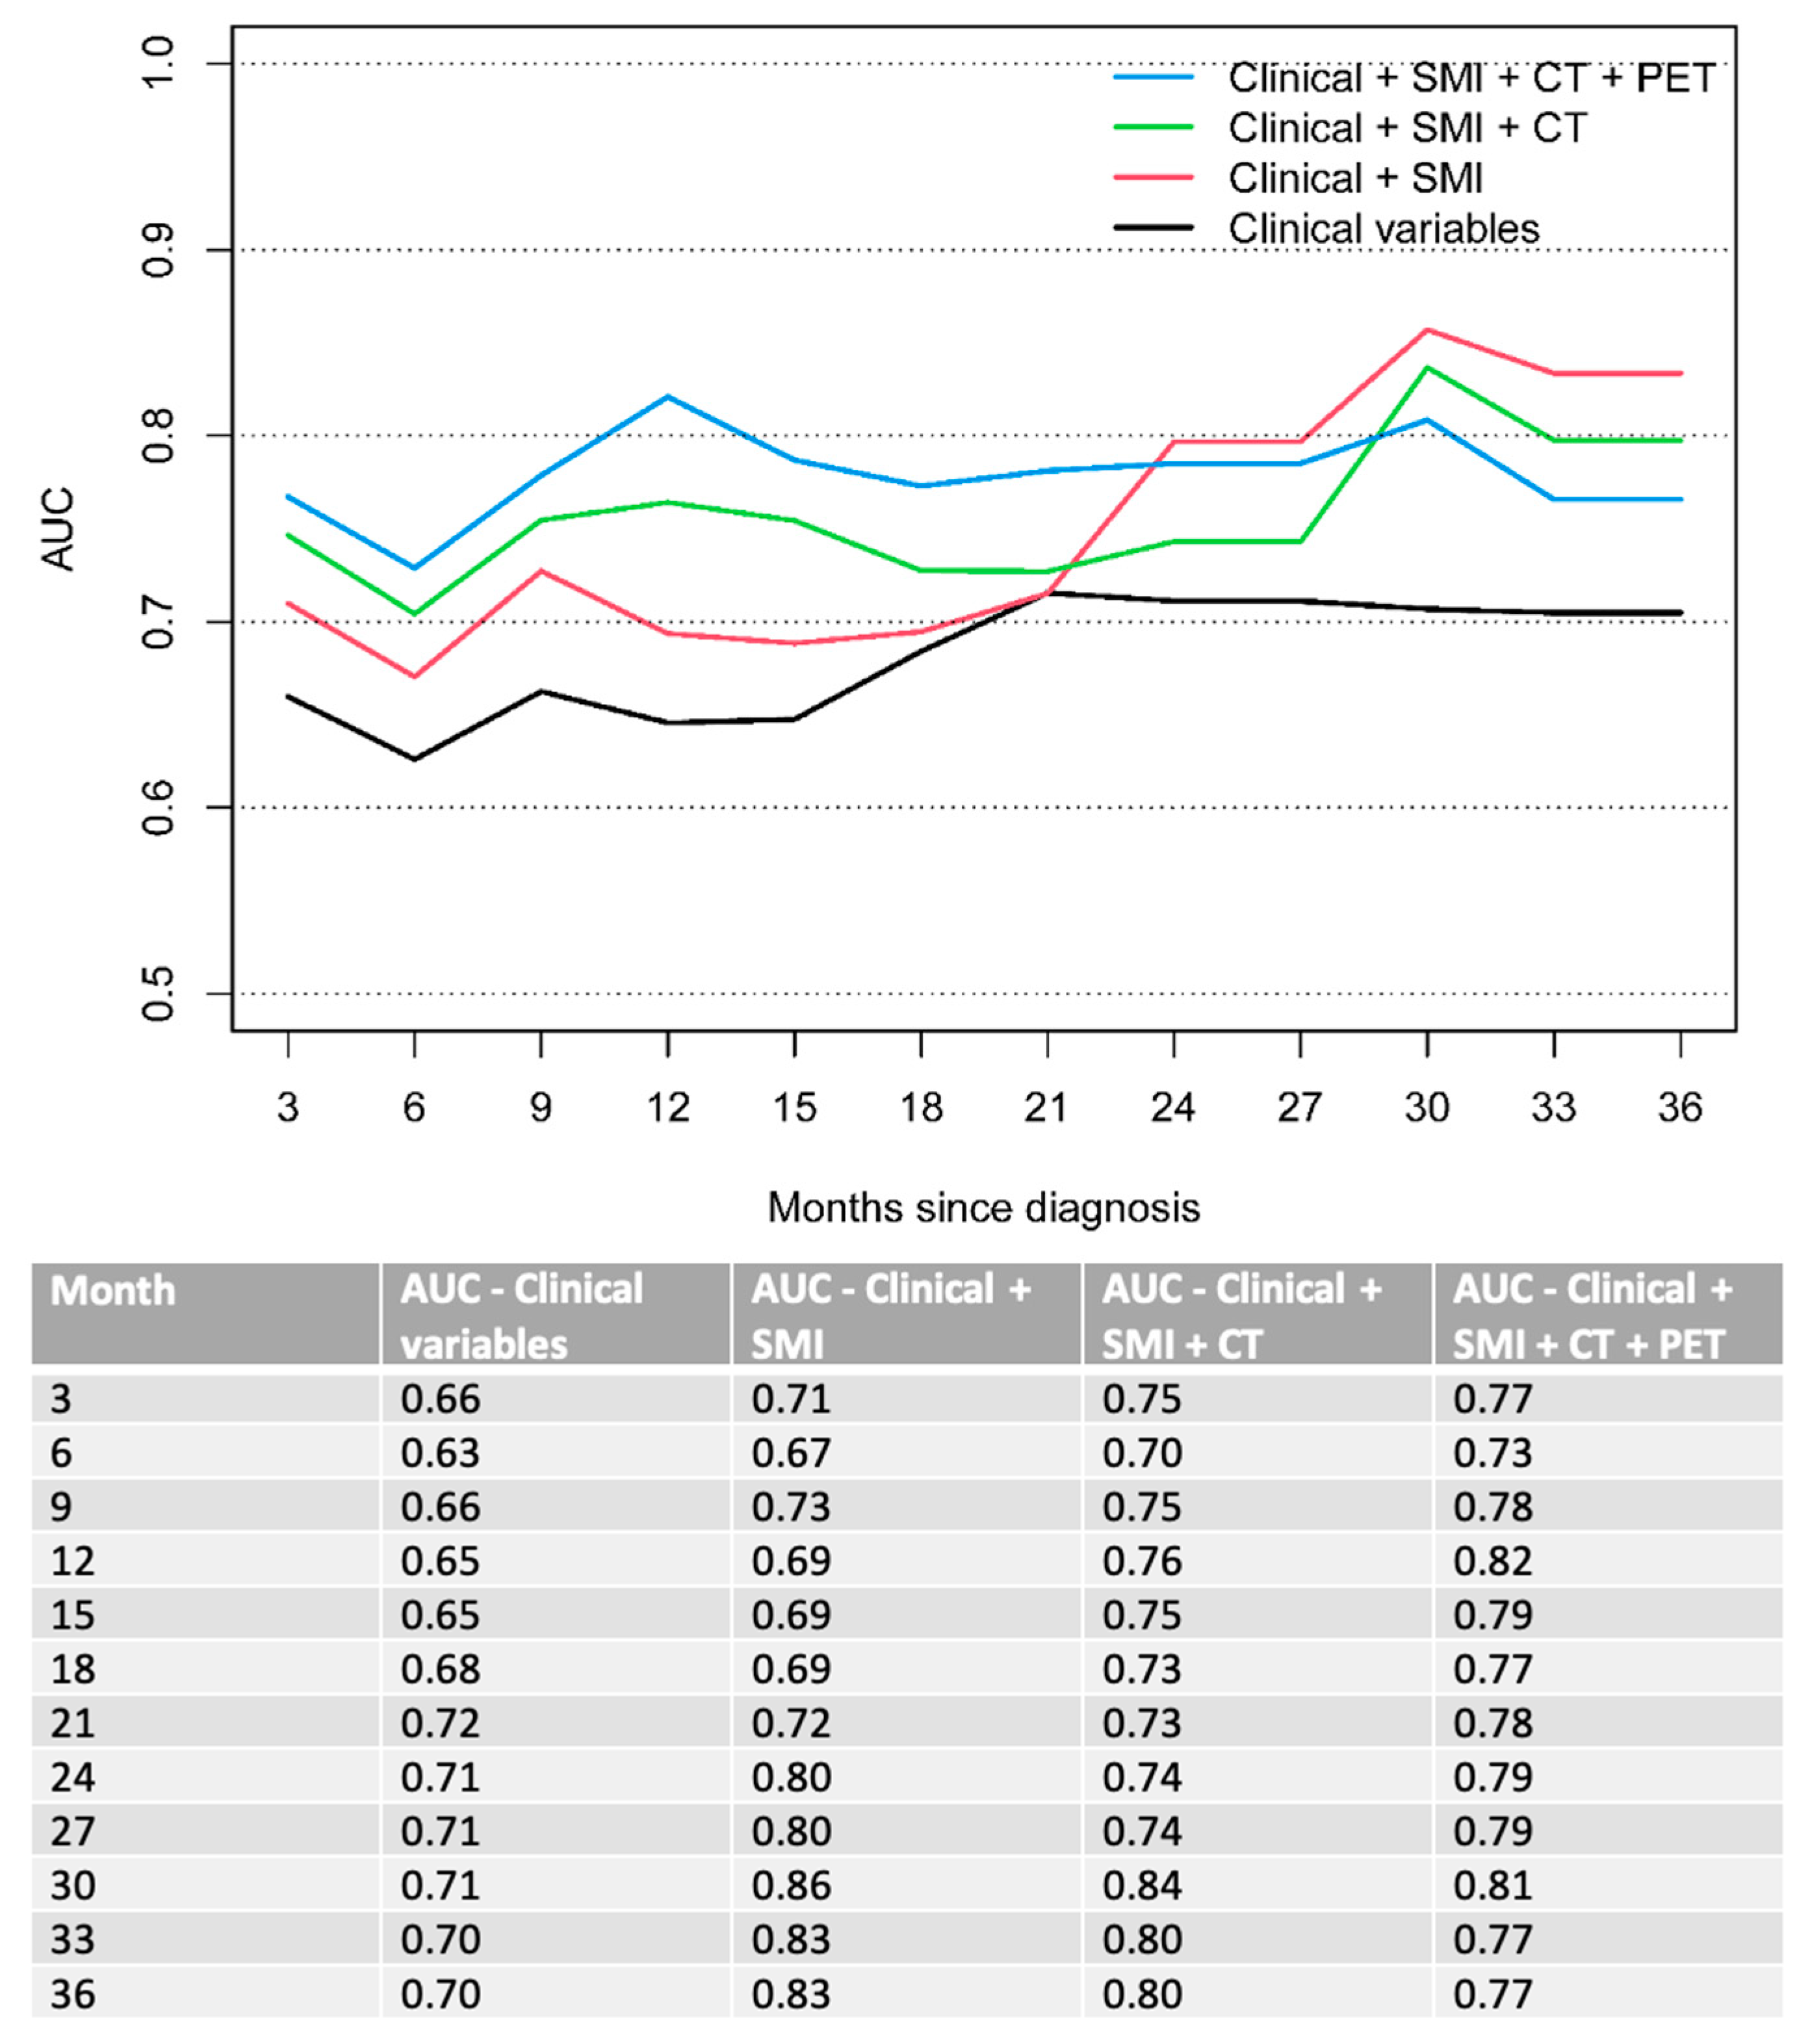

3.2. Multivariable Analysis